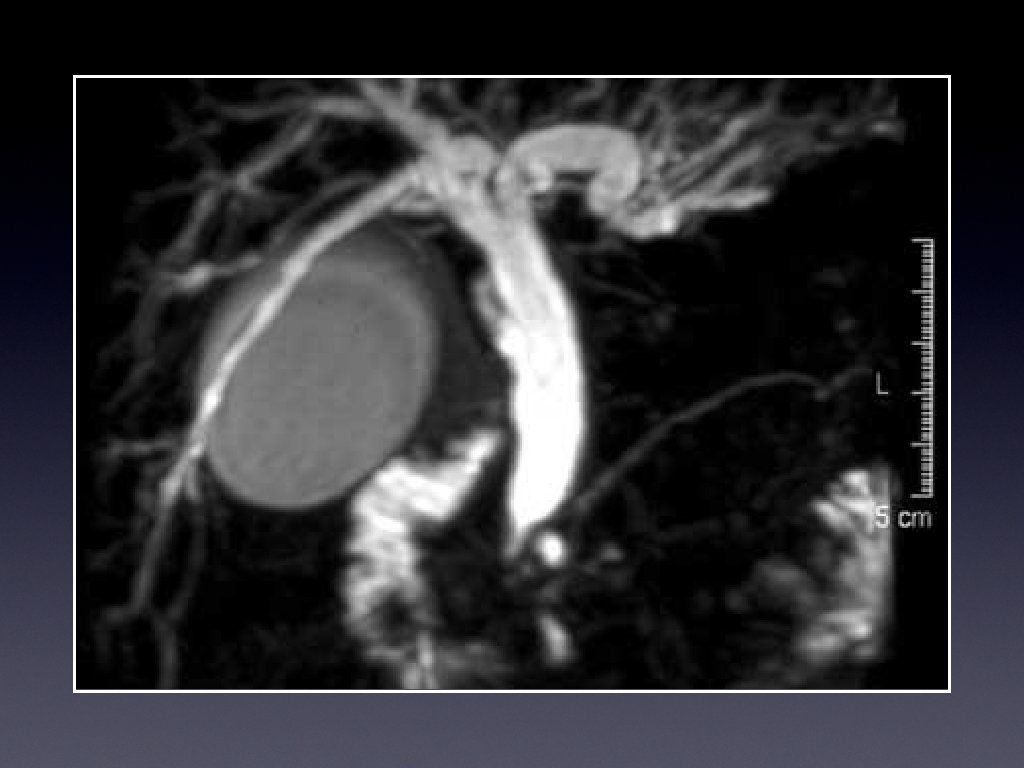

Investigations • Ultrasound • CT for evaluation, and full staging • Magnetic resonance cholangiography (MRCP)